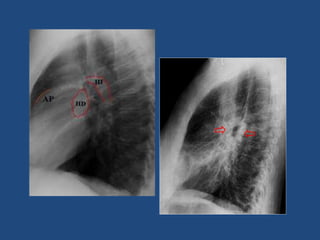

El hilio izq., se sitúa mas alto que el derecho

En la incidencia lateral la disposición del hilio es como sigue:

 El bronquio lobar superior derecho se la ve sobre la

parte inferior de la tráquea de forma circular

 El bronquio del lóbulo superior izquierdo se sitúa mas

abajo es alargado

 La arteria pulmonar derecha origina una imagen

radiodensa y circular situada delante de la Carina

(bifurcación traqueal)

 La arteria pulmonar izquierda tiene una forma tubular,

situada un poco detrás de la Carina y paralela al arco

aórtico, de densidad más baja que la arteria pulmonar

derecha

 Las venas pulmonares de cada lado están situadas

debajo de las arterias pulmonares correspondientes